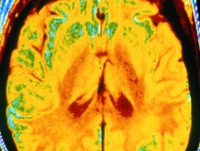

• Neuroimaging. КТ или МРТ головного мозга, позвоночные структуры используются для дифференциальной диагностики с другими потенциальными поражениями центральной нервной системы, когда диагноз не может быть поставлен каким-либо другим способом. Методы также информативны в случаях церебральной атрофии, поскольку они позволяют обнаружить расширение желудочков, лейкоарайоз, спайки арахноидальной мембраны. При необходимости оценивают уровень метаболизма глюкозы в центральной нервной системе с помощью ПЭТ-КТ.